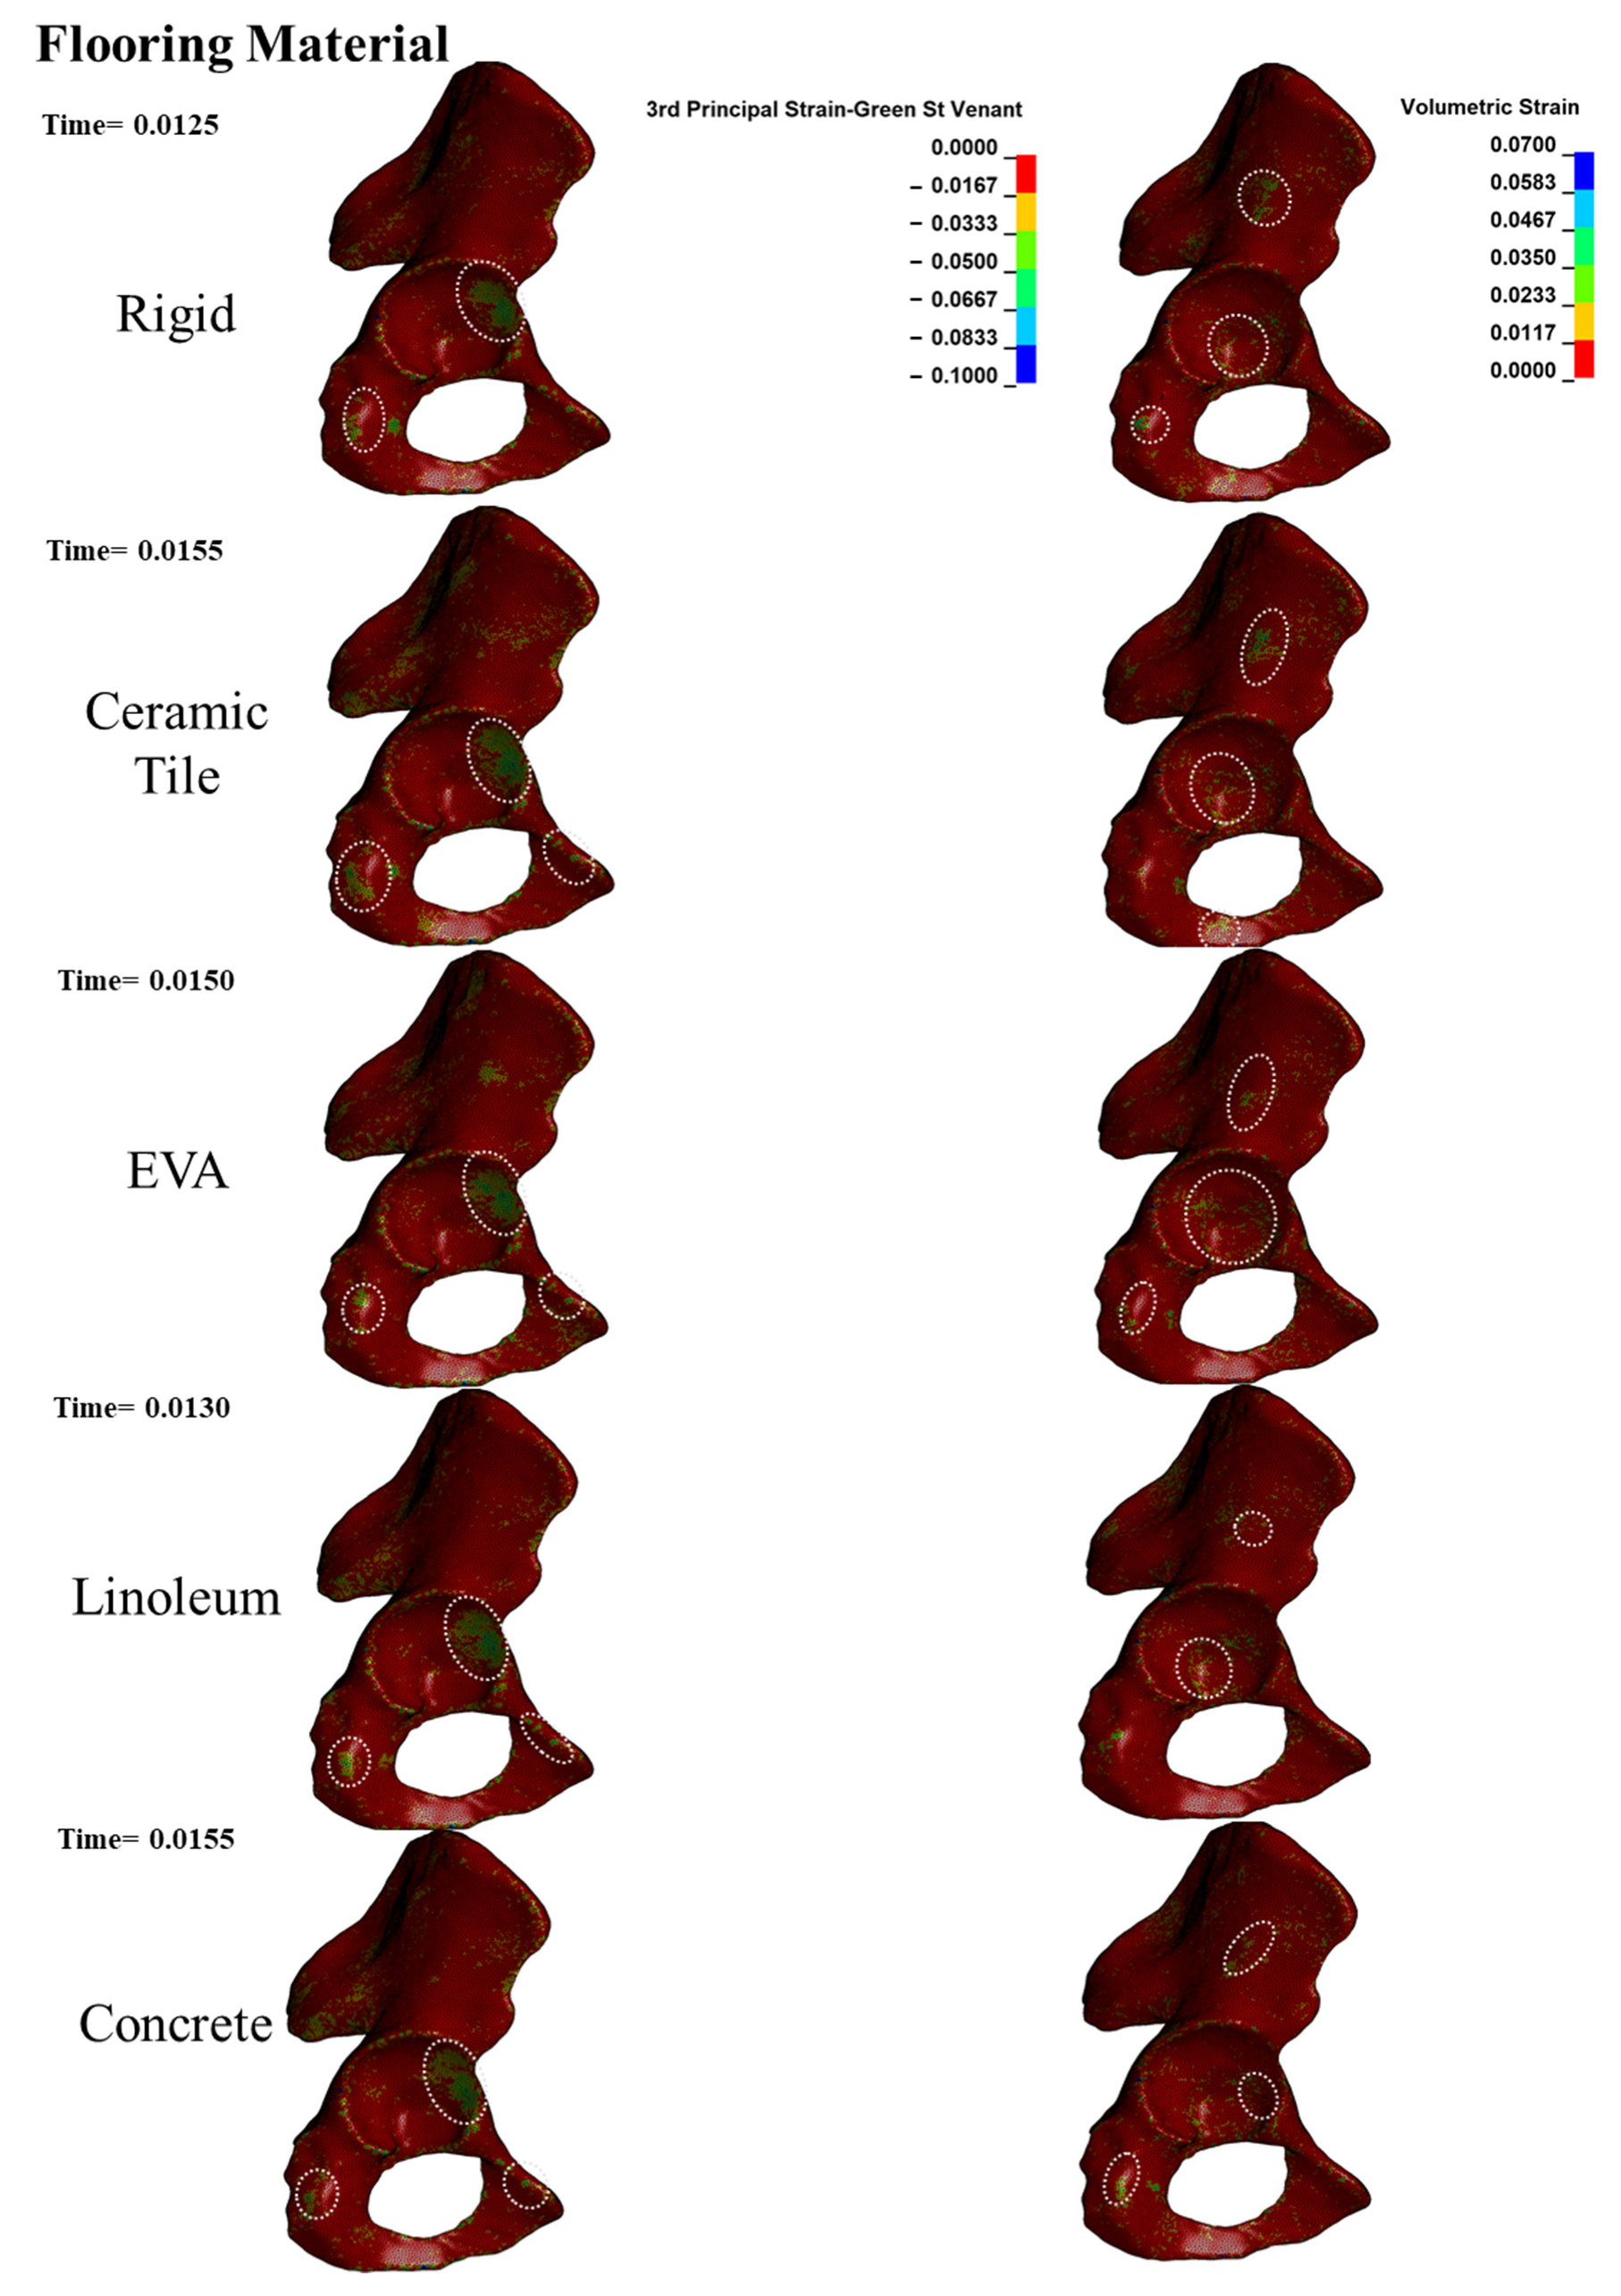

Appendix A.1. Acetabular Cortical Thickness